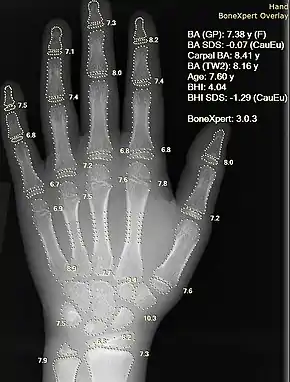

Information can take the form of images, sound, video or other multimedia. Bits of information can be streamed via signals. Its processing is the central notion of informatics, the European view on computing, which studies information processing algorithms independently of the type of information carrier – whether it is electrical, mechanical or biological. This field plays important role in information theory, telecommunications, information engineering and has applications in medical image computing and speech synthesis, among others. What is the lower bound on the complexity of fast Fourier transform algorithms? is one of unsolved problems in theoretical computer science.

![]() |

| FFT algorithms | Image processing | Speech recognition | Data compression | Medical image computing | Speech synthesis |